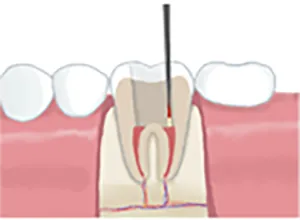

• 根管内の洗浄

3根管内の洗浄

根管内を薬液で洗浄消毒して、細菌を隅々まで取り除きます。

• 薬剤充填

4薬剤充填

薬液を充填し、細菌が繁殖しないようにします。